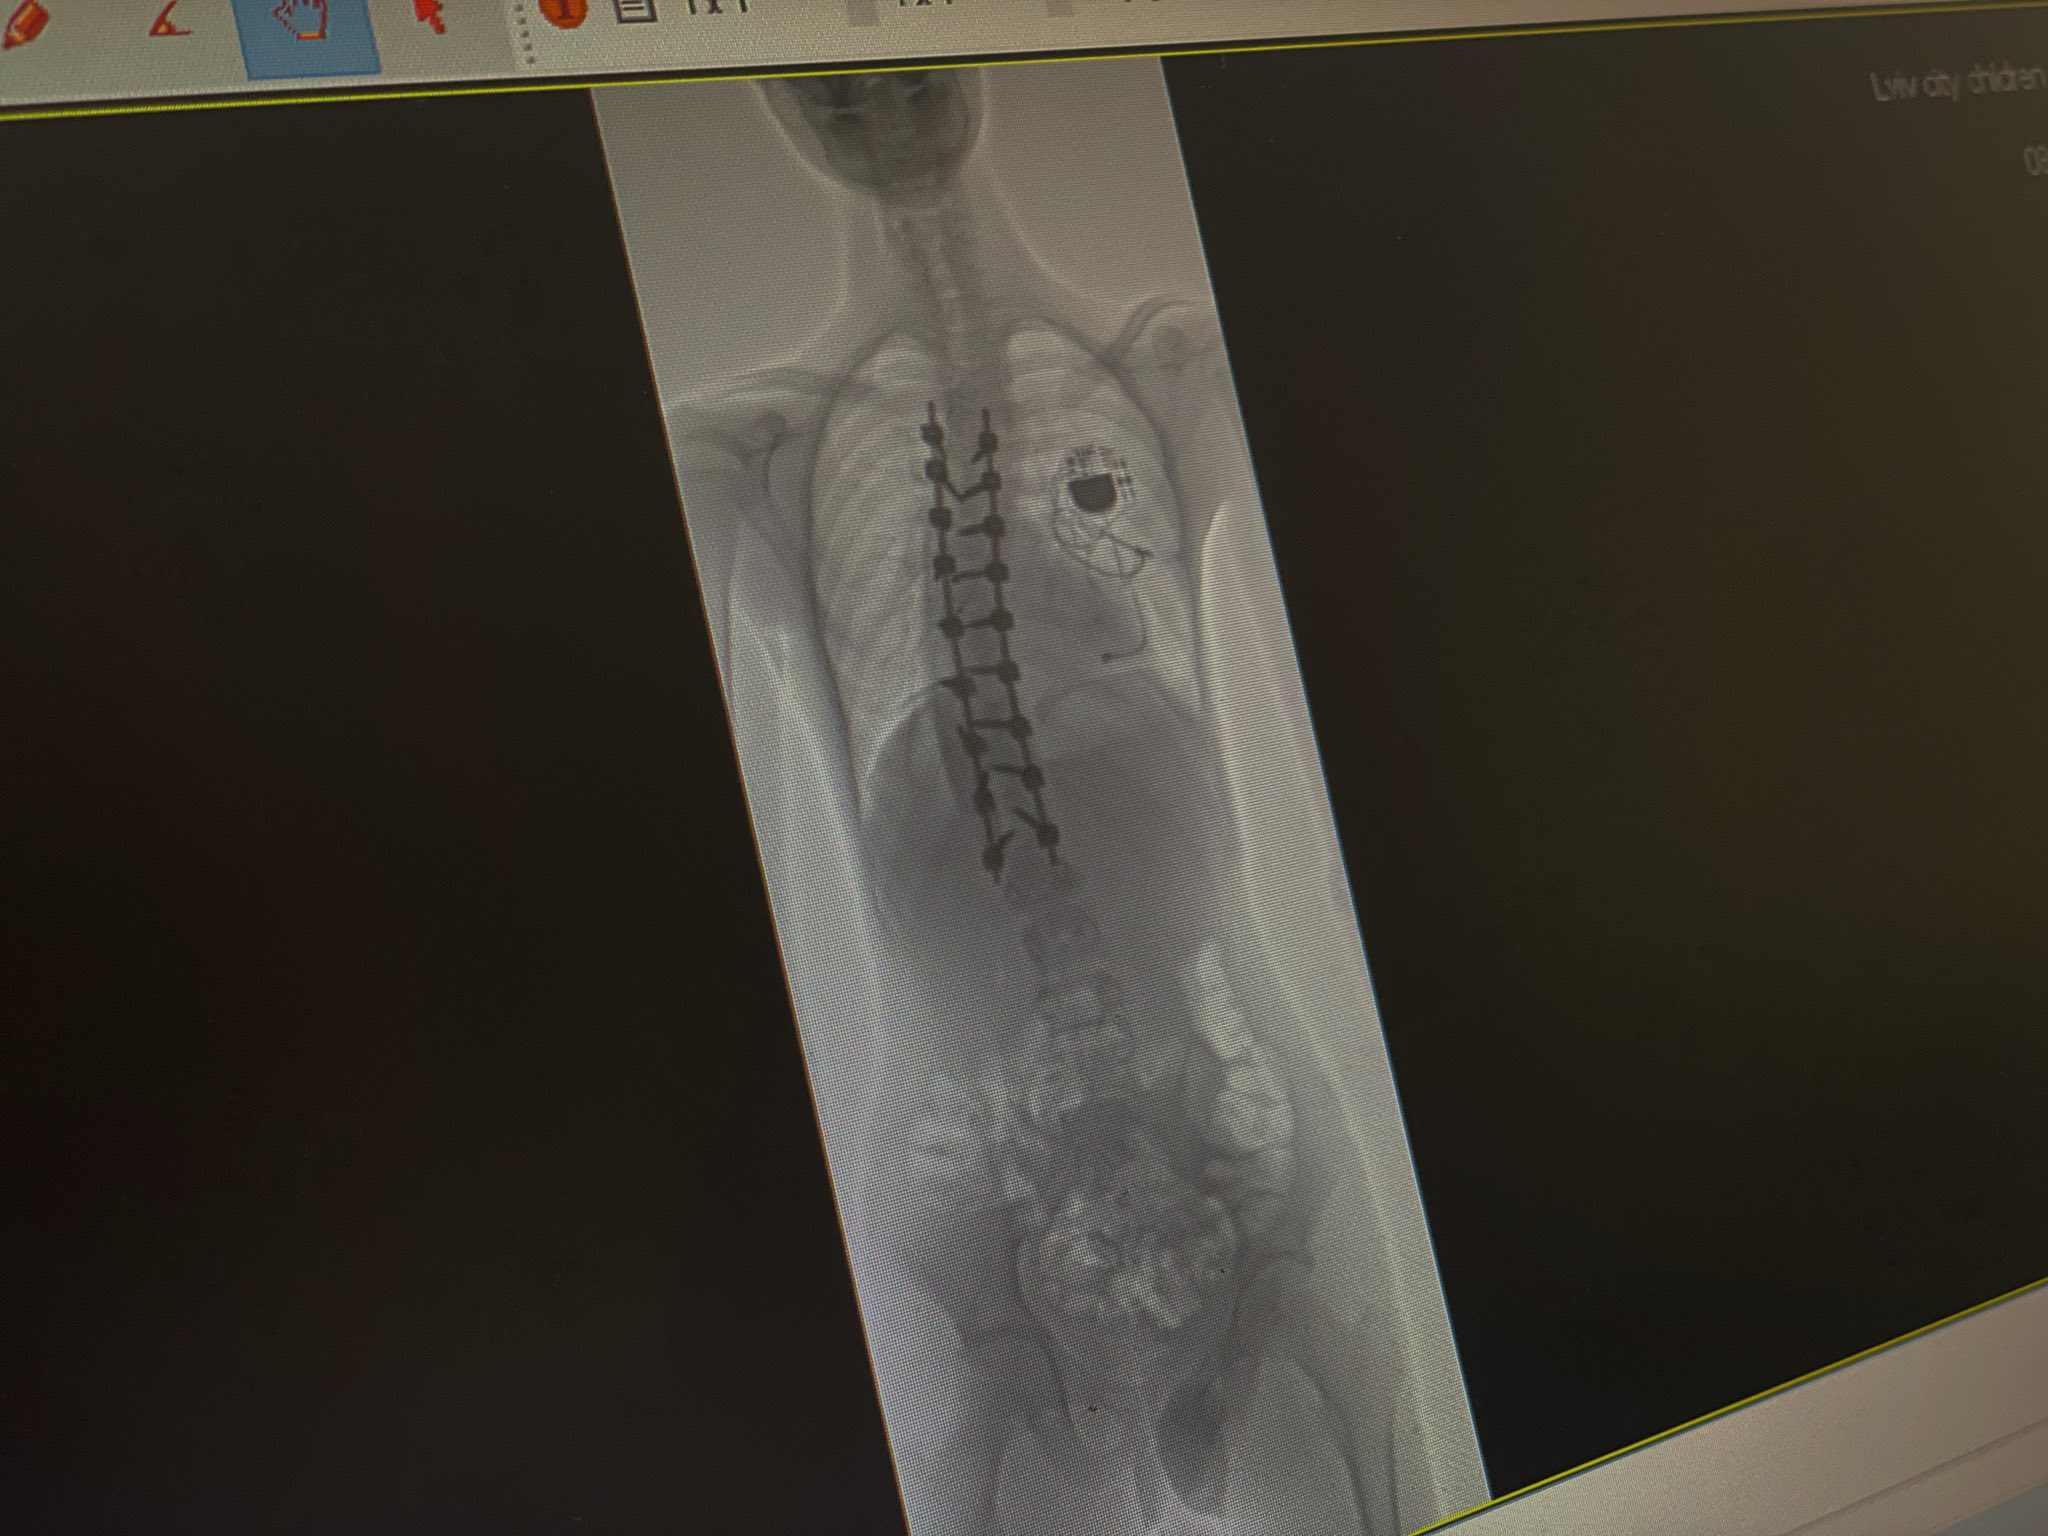

У дитячій лікарні Святого Миколая львівські медики разом з міжнародною командою на чолі з американським хірургом прооперували 16-річного підлітка зі сколіозом найважчого ступеня. Змалечку хлопець живе з кардіостимулятором, тож операцію з виправлення хребта було проводити ризиковано. Однак втручання пройшло успішно і викривлення хребта вдалося зменшити з критичних 80° до 25°. Про це повідомили у Першому ТМО 20 березня.

Операцію проводили у кілька етапів. Спершу лікарі обережно відокремили спинний мозок Ярослава від навколишніх тканин. За словами медиків, це був один із найнебезпечніших моментів. Далі встановили металеву конструкцію зі стрижнів і гвинтів, яка дозволила вирівняти хребет.

“У результаті викривлення вдалося зменшити з критичних 80° до 25° — це максимально можливий для безпеки спинного мозку показник. А завдяки ретельній підготовці вдалося уникнути кардіологічних ускладнень”, — додали медики.